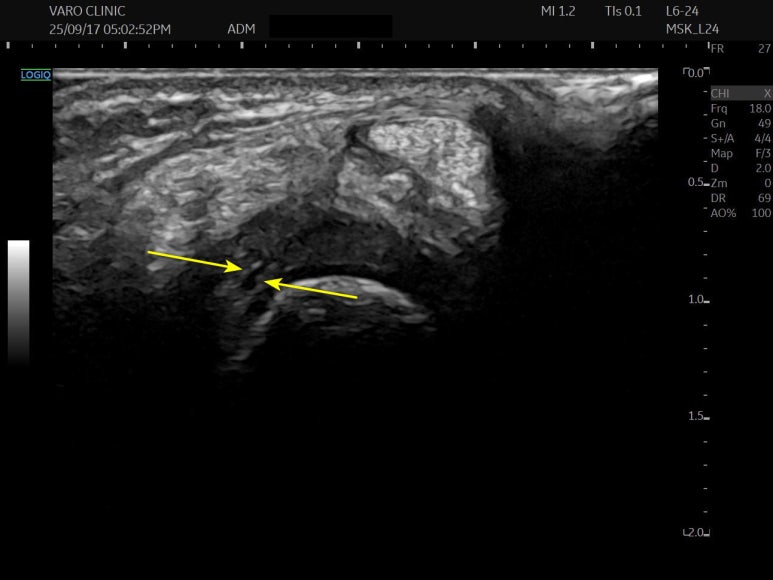

어떤 환자는 통증의 원인이

파열된 연골이 아니라

염증에 매우 민감한

'힘줄집(ECU sub-sheath)'에 있는 경우도

있습니다.

힘줄집은 통증 수용체가 워낙 많이 분포하는

민감한 조직이기 때문에,

이곳의 염증만 잘 치료해도

통증이 완전히 사라지는 경우도 있죠.

문제가 있는 혈자리를

초음파로 보면서

약침 주사를 시술합니다.